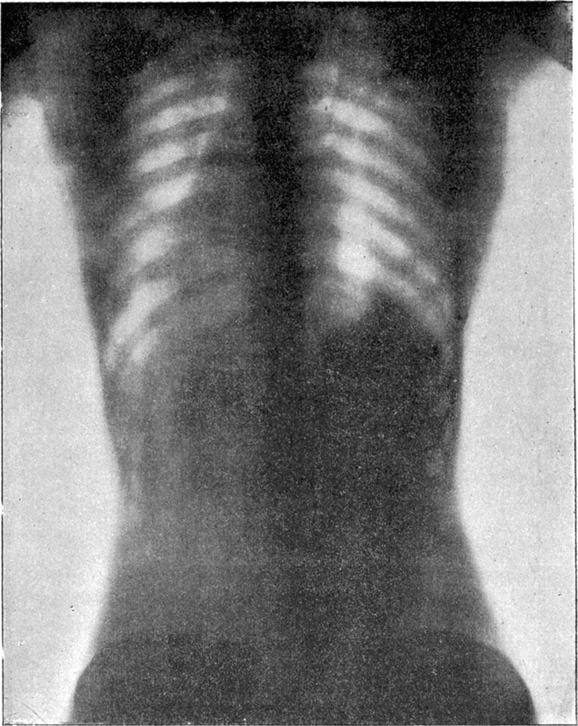

Hình ảnh chụp X-quang của người không mặc áo corset (trên) và người mặc chiếc áo thu nhỏ eo này (dưới).

Khi áo corset trở thành một xu hướng trong những năm 1890, mọi thứ càng trở nên nguy hiểm khi chúng ảnh hưởng đến cả hông và cột sống của phụ nữ bởi họ mặc nó khá thường xuyên. Những người phụ nữ thuộc tầng lớp thượng lưu thường có cơ thể biến dạng đặc biệt với phần ngực, vai và cổ phình to, eo bị thu hẹp lại.

Bên cạnh đó, corset cũng được sử dụng như một hình thức giảm cân, vì vậy chúng khiến người mặc có thể ngất xỉu, tử vong do tràn khí màng phổi, xẹp phổi.